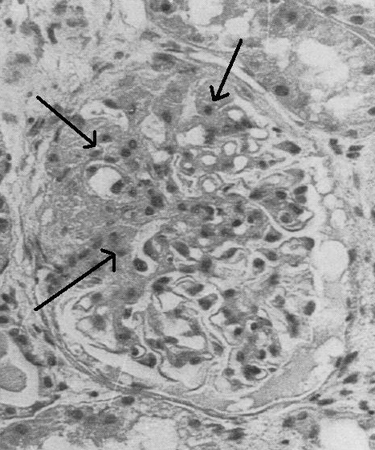

Characteristic features of focal segmental glomerulosclerosis (FSGS) lesions

Light microscopy of renal biopsy showing typical lesions of focal segmental glomerulosclerosis

Adapted from Nagi AH, Alexander F, Lannigan R. Light and electron microscopical studies of focal glomerular sclerosis. J Clin Pathol. 1971 Dec;24(9):846-50